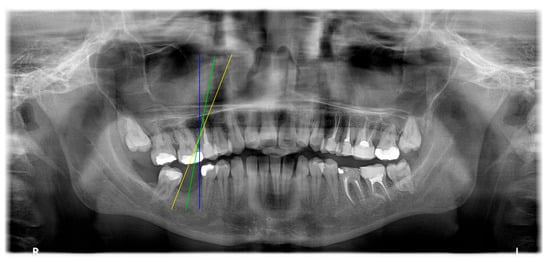

The angle bisector of the two auxiliary lines was then calculated using the angle bisector formula shown in (8), where (, , ) and (, , ) represent the coefficients of the two lines. The resulting internal angle bisector defines the preliminary implant pathway orientation derived by this framework. This bisector represents the most stable implant pathway orientation direction, ensuring that the implant avoids adjacent teeth and critical anatomical structures while maximizing bone–implant contact area. Such orientation enhances osseointegration stability and prevents complications from improper angulation, such as malocclusion or uneven stress distribution. The visualization of this process and the algorithmic design are presented in Figure 8. Finally, the auxiliary pathway generated by the algorithm was compared and overlapped with the implant pathway orientation annotated by dentists on the images to evaluate the predictive capability and accuracy of the model. The overlap results serve as a basis for further model optimization and provide valuable reference information for clinical application.

Figure 8.

Auxiliary lines are derived from adjacent teeth, the blue and yellow line is the result of implant pathway orientation visualization algorithm, and the green is the best implant pathway orientation.

3.3. Comparison with Clinical Ground Truth and AI-Assisted Framework

This subsection presents a comparison between the dentist-defined clinical gold standard and the predictions generated by our AI-assisted framework to evaluate the reliability of implant pathway orientation. The result is shown in Table 10, the preserved DPR validation set was used for verification, and the AI-assisted framework results were overlaid onto the original DPR images to provide a clear visualization. The AI-assisted framework pathways (green lines) were highly consistent with the dentists’ ground-truth annotations (black lines). Quantitatively, the mean squared error (MSE) between the predicted implant direction and the dentists’ planned results was only 1.537° across multiple test images. This minimal deviation validates the proposed system’s technical feasibility. It highlights its clinical potential to provide accurate and stable guidance for implant placement, thereby reducing the risk of misalignment and supporting efficient preoperative orientation.